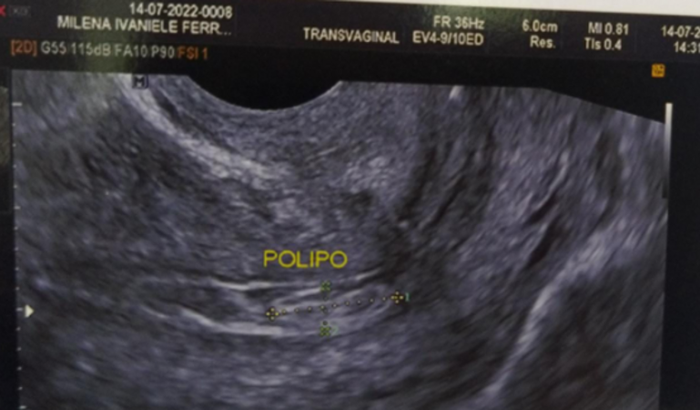

Olá, me chamo Milena e preciso arrecadar esse valor pra realização dessa pequena cirurgia com biópsia.

Estou com sangramento há mais de 20 dias devido a esse problema, cólicas horríveis, não consigo comer, devo estar anêmica.